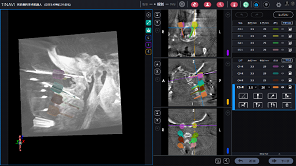

于是,吴超团队基于患者的颈椎三维模型,模拟置入颈椎椎弓根螺钉,并设计导航模板进行3D打印,术中结合骨科机器人导航,精准置入了颈椎椎椎弓根螺钉。

基于3D打印模型规划钉道

机器人联合3D打印导板辅助置入颈椎椎弓根螺钉